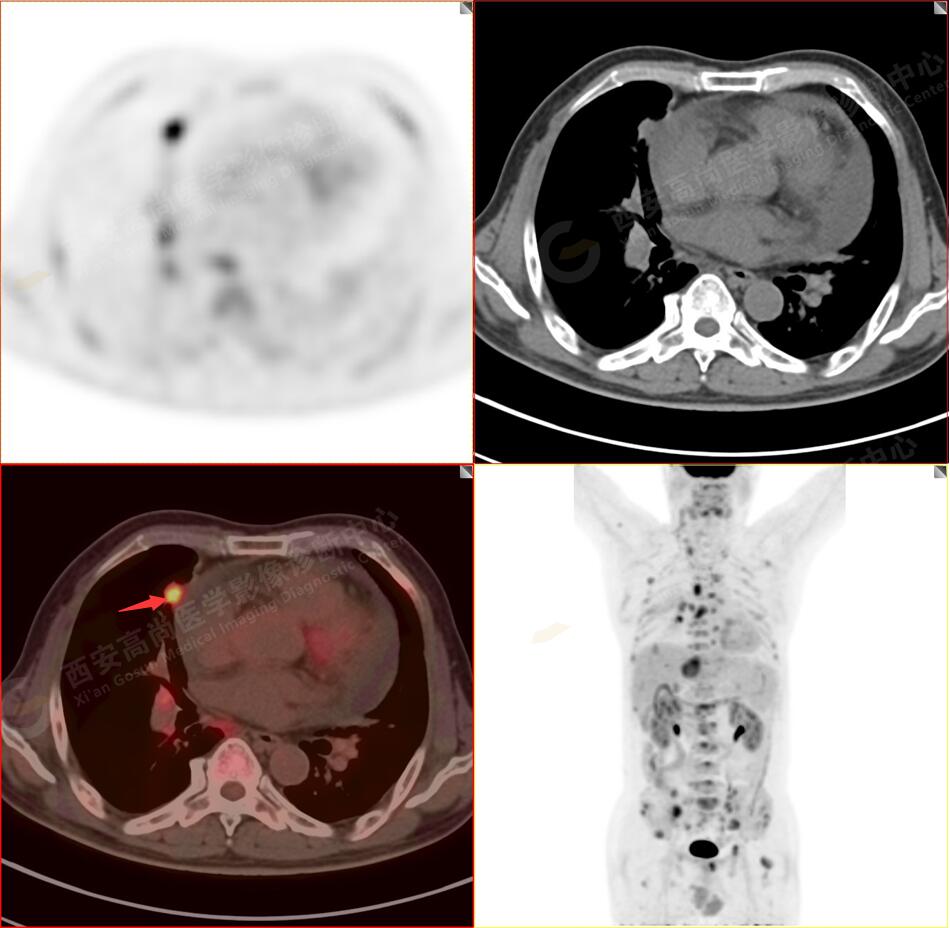

2.以下為全身多發(fā)轉移灶

5.右側肱骨上段、左側肩胛骨、右側鎖骨胸骨端、胸骨、雙側多發(fā)肋骨、脊柱多發(fā)椎體及附件、雙側髂骨、雙側髖臼、雙側恥骨、雙側肱骨上段多發(fā)成骨性病變,呈不同程度FDG代謝異常增高,考慮為多發(fā)骨轉移瘤。